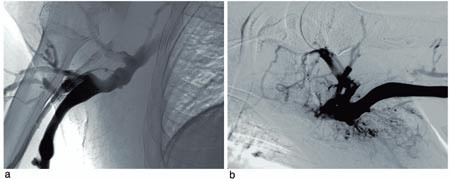

Røntgenundersøkelser. CT-undersøkelse viste trombemasser i v. jugularis og v. brachiocephalica på begge sider. Venografi bekreftet funnene og viste også trombemasser i v. subclavia på begge sider (fig 1). V. cava superior var også okkludert av trombemasser.

Behandling og forløp. Trombolysekateter (5F Jetlysis, Angiomed, BardInc, Karlsruhe, Tyskland) ble først lagt inn fra høyre arm, og det ble gitt alteplase 1 mg/t og samtidig heparininfusjon i trombolysekateteret. Bolusdose av alteplase ble ikke anvendt, da pasienten var antikoagulasjonsbehandlet med warfarin. Venografi etter ett døgn viste fin rekanalisering av høyresidige overarmsvener og delvis rekanalisering av de venstresidige overarmsvener samt v. cava superior. En subtotal stenose i v. cava superior ble avdekket (fig 2 a). Lumen i det stenoserte området hadde en diameter på 2 – 3 mm, og spissen av shunten endte i dette området (fig 2 a). Det ble satt inn en stent (14 x 40 mm Symphoni stent, Boston Scientific, USA) som ble dilatert til 10 mm (fig 2 b). Trombolysekateter ble så lagt inn fra venstre arm, og det ble gitt infusjon av alteplase og heparin. Venografikontroll viste komplett trombolyse etter totalt to døgns trombolytisk behandling. Pasienten ble behandlet med lavmolekylært heparin og warfarin inntil INR hadde vært i terapeutisk område (2,5 – 3,5) i to døgn. Ved utskrivning to uker etter innleggelse var pasienten fullstendig restituert. Ved kontroll etter seks måneder var han klinisk i fin form, og venografi viste åpne vener.